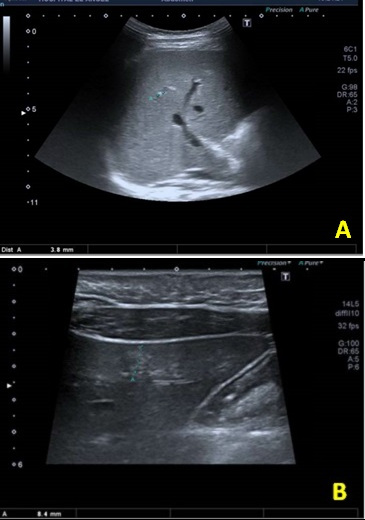

La ecografía abdominal mostró varias lesiones hiperecogénicas pseudonodulares en ambos lóbulos hepáticos, menores de 5 mm, salvo una en lóbulo izquierdo de 8 mm, sugerentes de hemangiomas hepáticos focales sin shunt arteriovenoso o portovenoso (Fig. 1). Resto de parénquima hepático sin hallazgos.

Figura 1. (A). Hemangioma 3,8 mm. (B). Hemangioma 8,4 mm lóbulo izquierdo

Figura 1. (A). Hemangioma 3,8 mm. (B). Hemangioma 8,4 mm lóbulo izquierdo.